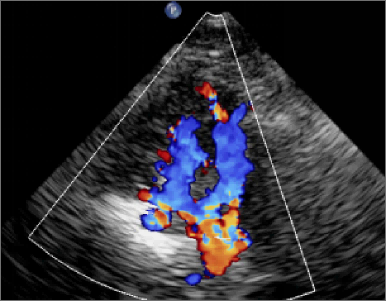

埃斯科核心实验室(IsCore image corelab) 是晓得(北京)商业发展有限公司旗下 的独立第三方核心实验室。由经验丰富的临床专家团队和影像放射专家团队组成, 致力于帮助临床医生和医疗领域的公司进行细致的、标准的、规范的影像管理和 判读。IsCore 影像实验室提供的影像判读数据已经为多家医疗机构的科研课题提 供数据支持,同时也已经协助国内外数个产品研发上市提供科学帮助。我们实验室的影像评价者均在国内顶尖专科医院接受过临床影像专业的系统学 习与规范培训,有多年的临床工作经验,以及强大的技术支持,能准确判读 MRI, HRMRI, DSA, OCT, CFD, VU 等影像,给出标准规范的报告结果,最低限度减少 了人为因素对试验结果的影响有助于科研成果产出和产品研发。